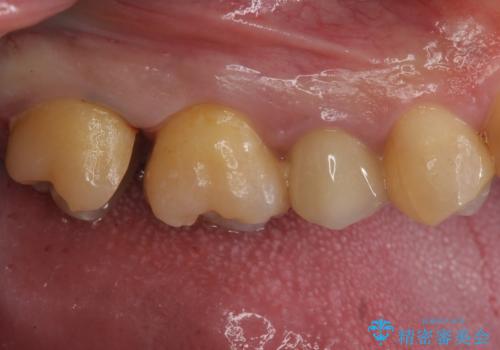

放置していた虫歯 セラミックインレーによる治療

- 食事の際に右上の奥歯が痛むので診てほしいとのことで来院。

視診では明らかに食べ物が詰まっているのがわかり、レントゲン写真では大きな虫歯の像が確認されました。

虫歯の大きさ次第でクラウンかインレーのどちらかになるだろうとご説明させていただき、今回はセラミックインレーでの治療となりました。